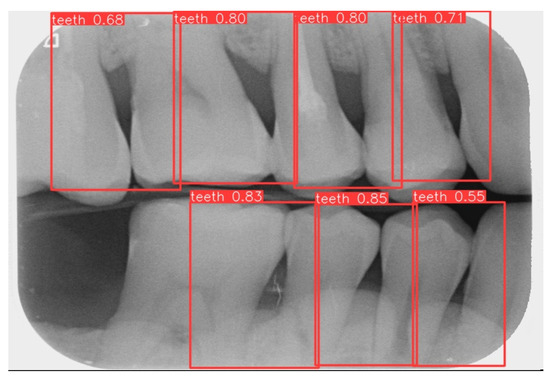

2.2.1. Annotation of Tooth

Labeling was used as a tool, and by utilizing the rectangular tool, the marking range was from a single tooth section to another tooth section, which helps to accurately mark the actual condition of the gingiva around the middle of the tooth. Finally, the image was saved as a YOLO file and labeled as shown in Figure 2a. This process highlights the target area in the image and provides clearer information for CNN training.

Numerous object detection models have been developed, such as the R-CNN series, Single Shot MultiBox (SSD), RetinaNet, and YOLO. Due to the complexity and variability in tooth alignment in each patient, the gums need to be separated at the BW film; YOLOv8 is the best model utilized in BW image segmentation for Angular Erosion. The YOLO model has an advantage in detecting the foreground and is highly efficient in considering the global information of the image and making judgments, and it also utilizes an anchor-free design. In the past, anchor frame detection was utilized to envelop various objects with predefined anchors. Regression adjustment was carried out through a series of operations, and the most accurate frames were retained using non-maximum suppression. Anchor-free detection predicts the center point of an object directly from the image to learn its location and size. This method helps detect objects with greater accuracy in various complex scenes, such as accurately locating teeth. Target detection of the vertical biting airfoil image is then performed by the trained YOLO model, as shown in Figure 2b.

3.1. Image Segmentation

This study uses YOLOv8 to detect the gingiva between each tooth and record its coordinates. The parameters are listed in Table 6. The final target detection results of this study are shown in Figure 8. The comparison between the YOLO detection model and other studies is presented in Table 7. The image shows that the gum features are completely preserved, providing a reliable basis for CNN.

Figure 2. Image annotation and segmentation. (a) Image Annotation Diagram. (b) The tooth segmentation result.

Figure 8. YOLOv8 detection result.